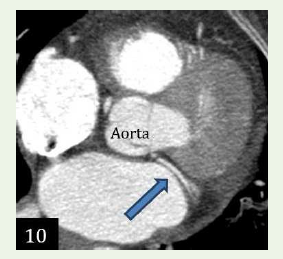

Case 4: A 68-year-old female with c/o chest pain, case of hypercholesterolemia and diabetes and concentric le ventricular hypertrophy in echocardiogram, demonstrated an anomalous origin of Left circumflex artery from the right coronary sinus with retro- aortic course.

Figure 10:Maximum intensity projection reconstruction and 3D volume

rendered reformation shows an anomalous origin of Left circumflex artery

from the right coronary sinus with retro-aortic course.